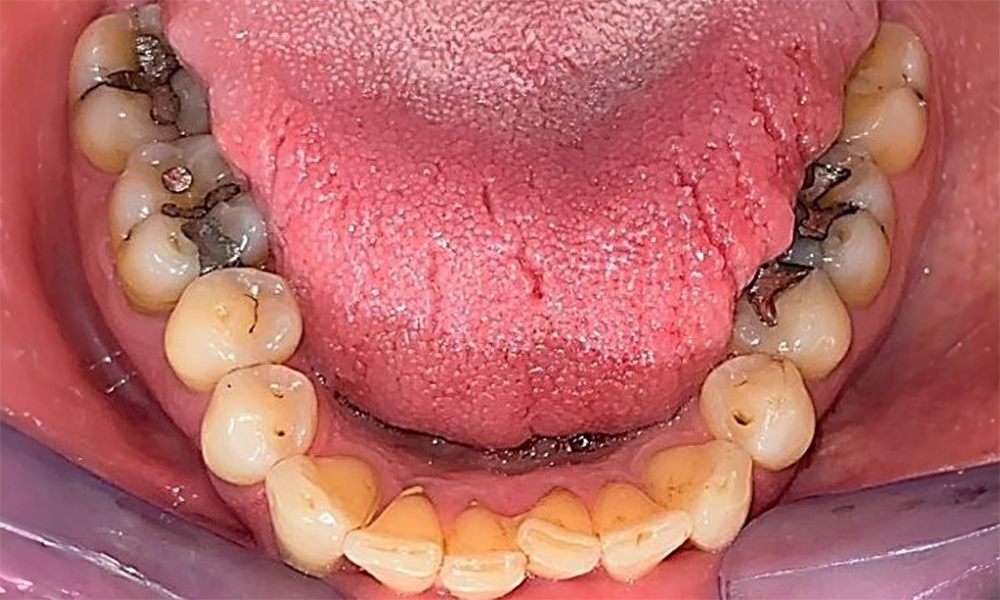

Оклузален изглед на долната челюст, показващ съществуващите възстановявания.

Фиг. 6 Оклузален изглед на долната челюст, показващ съществуващите възстановявания. © д-р Р. Крапф

Пациентът има пълно съзъбие с 28 зъба, което включва амалгамни и композитни пломби в областта на моларите и премоларите. На зъб 14 има видима клинична маргинална празнина. Зъб 27 има адекватна златна инкрустация. Налице са и генерализирани атриции и абразии. (фиг. 2, фиг. 3, фиг. 4, фиг. 5, фиг. 6)